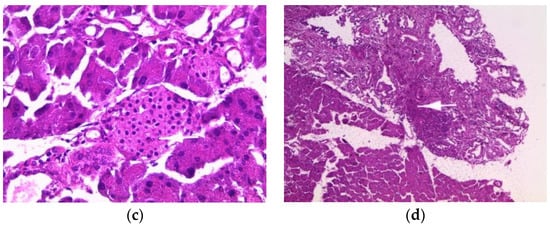

The pancreas of normal mice showed pancreatic acini (PA) with normal histological appearance and normal inter-acini and interlobular spaces (Figure 3a). Pancreas histology of mice treated with the aqueous extract (200 mg/kg) showed only intra-pancreatic inflammation (Figure 3b). Additionally, pancreas sections from mice treated with the ethanolic extract showed only minimal focal intralobular inflammation (Figure 3c), while the pancreas of mice treated with the methanolic extract showed intra-pancreatic inflammation and increased plasma cells (Figure 3d).

Figure 3.

Histopathology of the pancreas. Histological sections were visualized by hematoxylin and eosin (H and E) staining and observed under a light microscope (OPTIKA Microscopes, Italy) at 40× magnification. (a) Control mice, (b) mice treated with aqueous extract of E. guttatum (200 mg/kg), (c) mice treated with ethanolic extract of E. guttatum and (d) mice treated with methanolic extract of E. guttatum.

Histopathological studies serve as supportive evidence for hematological and biochemical analyses [31]. The photomicrographs of sections of the liver, kidney and pancreas of mice treated orally with extracts of E. guttatum at a dose of 200 mg/kg for 28 days showed histological changes such as an intralobular mononuclear inflammatory focus, a mononuclear inflammatory focus around the centrilobular veins (CLV), hydropic cytoplasmic degeneration of hepatocytes, binucleate cells and a nucleus, a low-bulk, dark-pigment glomerular lesion, interstitial inflammation, plasma cells in the interstitium, and intrapancreatic inflammation. Therefore, these histopathological findings corroborate the biochemical results, and a chronic study is necessary for a complete understanding of the hepatoxicity of this plant.